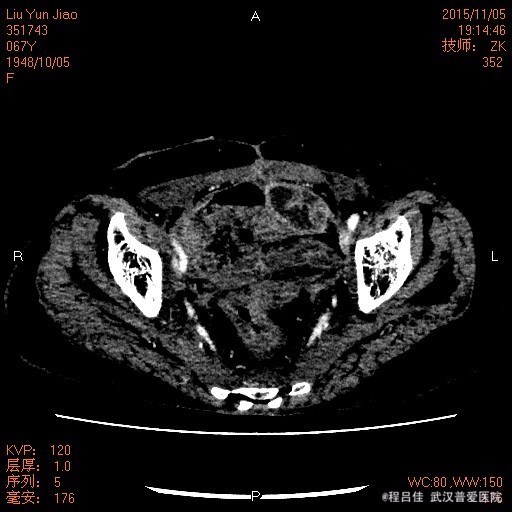

查体:腹部平坦,无胃肠型,无压痛及反跳痛,肠鸣音正常,阴道仍有粪渣样物质排出。 辅查: 膀胱镜检查:膀胱阴道瘘诊断明确 腹部CT:1.“宫颈癌行子宫全切术后+化疗后+回肠代膀胱造瘘术后+右肾造瘘术后"改变:回肠代膀胱;膀胱积气及膀胱壁增厚,膀胱后壁欠连续,并见后凸小囊腔,由于其后方阴道及直肠显示欠清楚,考虑膀胱阴道瘘可能性大,未能确定是否与直肠相通,请结合临床。 2、盆腔前腹壁下包裹性积液积气形成;腹壁切口区改变,盆腔术区肠管聚拢、结构紊乱,考虑粘连伴小肠低位不完全性机械性肠梗阻。 3.胆囊多发结石,肝S6囊肿,右肝内胆管轻度扩张。